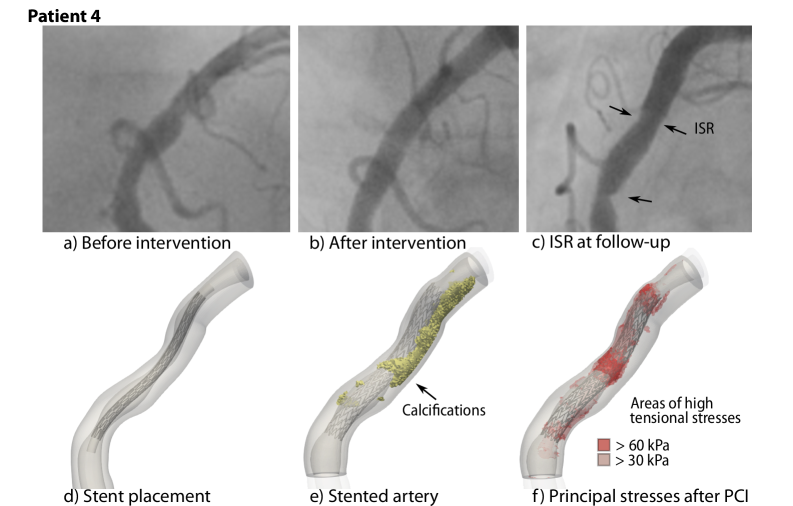

Appendix D Stent placement and correspondence to angiography data

In the following, we compare the simulation results of Patient 1, 2, 3, and 4 to the angiography imaging data, see Fig. 11, 12, 13, and 14, respectively. We select single frames during the diastole from the respective angiography data. For each patient, Subfigures a) and d) show the configuration before the intervention. Subfigures b) and e) show the angiography image after the intervention and the simulated stented artery. Subfigures c) and f) compare the follow-up angiography with the maximum stresses after the intervention.

Refer to caption

Figure 14: Stent placement and corresponding angiography data for Patient 4

Figure 18: First principal stress values in selected cross-sections during and after PCI; Patient 4. The plaque morphology is shown in the CCTA cross-sections and in the model. The stent cross-section is shown as black dots. Ca: Calcification.

The lesion in Patient 4 contains a large calcification, that is, similar to the pattern of Patient 2, arranged longitudinally with a switch to a circumferential pattern. Additionally, in the proximal section, there are smaller calcification blocks. In the proximal part, we observe high stresses opposite of asymmetric calcifications, especially in the thin-walled sections. The highest stress values occur in the section of the circumferential calcification. The media and adventitia experience lower stresses in calcified areas.